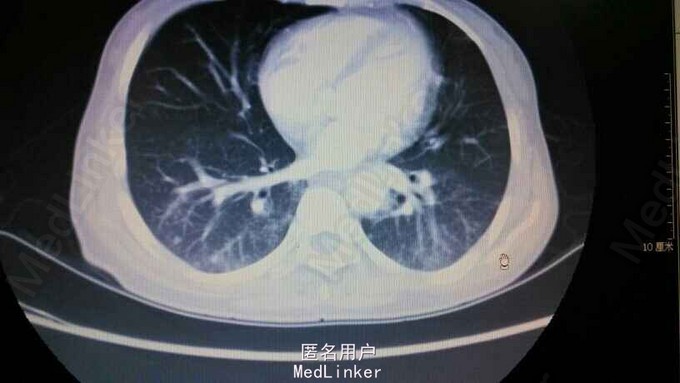

双肺呼吸音粗,双肺底闻及湿罗音。余无特殊。血象不高。抗肺炎支原体抗体阳性,滴度1:1280,后复查1:2560。支气管镜未见明显异常。胸部CT示双肺感染性病变

肺炎支原体肺炎干咳为主,无痰,以间质病变为主。